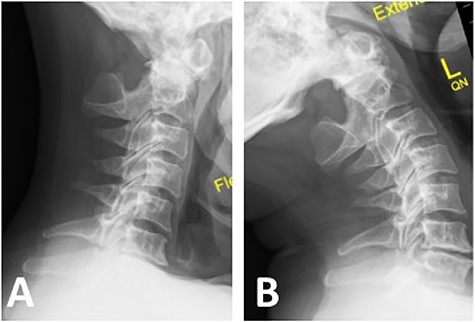

Computed tomography (CT) demonstrated non-union between the odontoid process and body of axis, as well as absence of the posterior arch of atlas (Fig. 1A). Magnetic resonance imaging revealed myelomalacia at the level of non-union likely due to repetitive dynamic compression (Fig. 1B). Flexion–extension X-ray films confirmed significant distraction and forward translation at the atlanto-axial joint (Fig. 2).

Note the absence of posterior arch of atlas (C1); (A) flexion X-ray revealed antero-inferior translation of atlas (C1) on axis (C2); (B) extension X-ray revealed postero-superior translation of atlas (C1) on axis (C2).